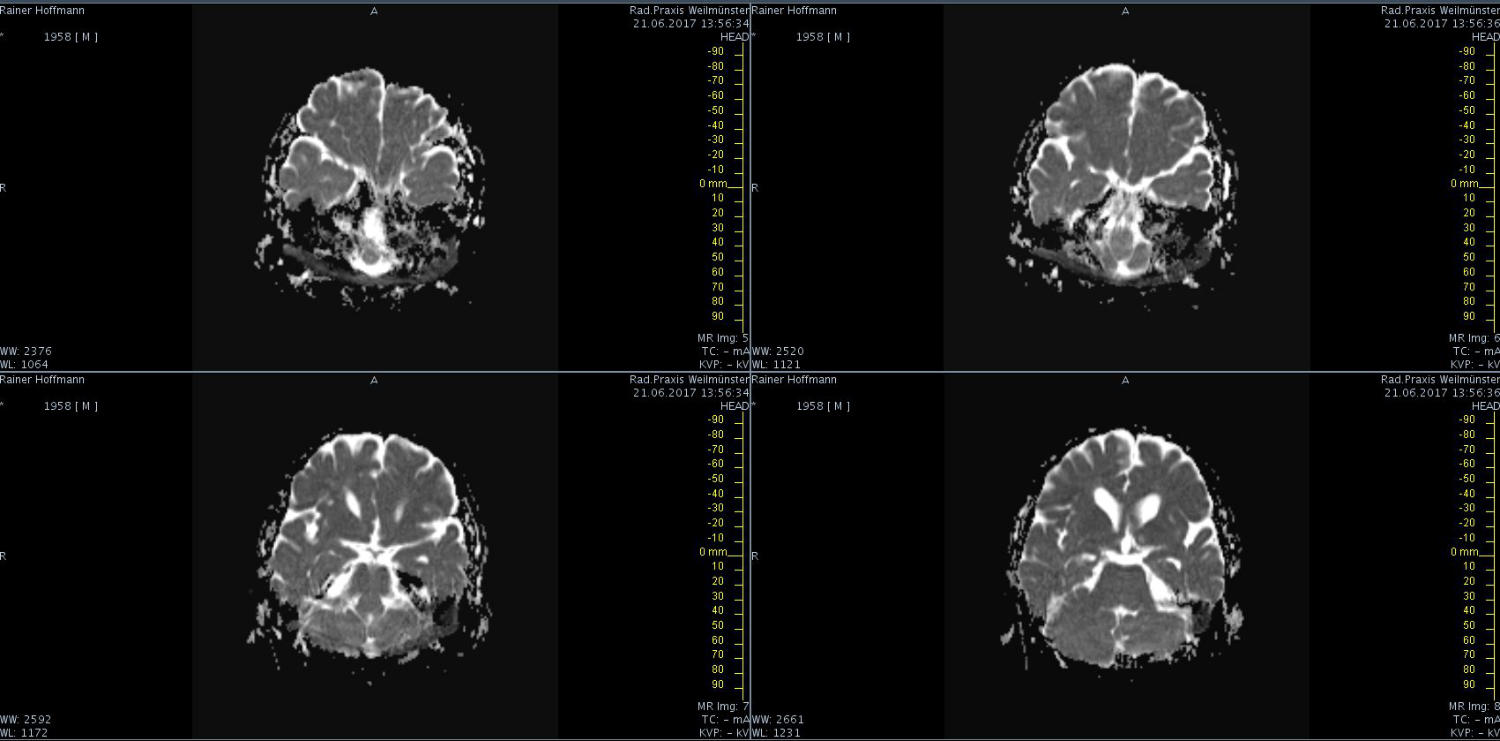

Das ist ja ganz toll, dass Ihr die Seite so schnell gefunden habt. Ich zeige euch jetzt ein ganz, ganz anderes Paßfoto von mir. Es könnte Ähnlichkeiten zu anderen lebenden oder bereits verstorbenen Personen geben. Wenn Ihr das erste Bild oben links anklickt wird es ver- größert dargestellt. Dann kann man mit den Pfeiltasten am unteren Bild- rand durch meinen Kopf blättern. Es gibt nicht viel zu sehen. Vielen Dank an Martina für Ihre Hilfe.

MRT